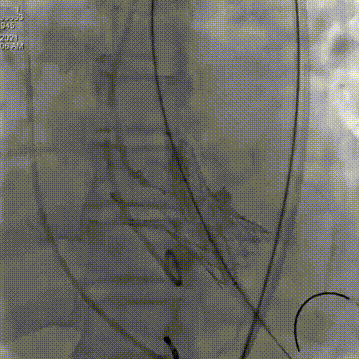

术中影像

主动脉根部造影可见重度钙化